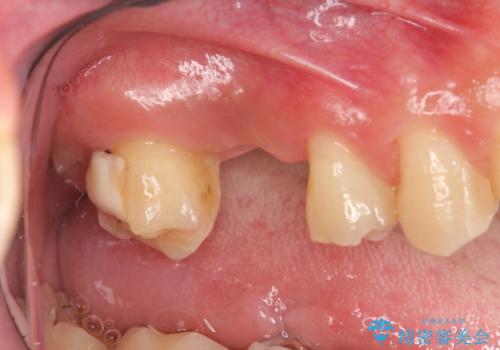

[歯周病治療] 歯周補綴 インプラント補綴

![[歯周病治療] 歯周補綴 インプラント補綴の症例 治療前](https://seimitsushinbi.jp/wp/wp-content/uploads/2020/03/067ed603e15bc4c623e950ffbd6c0829-500x350.jpg?v=1585493851)